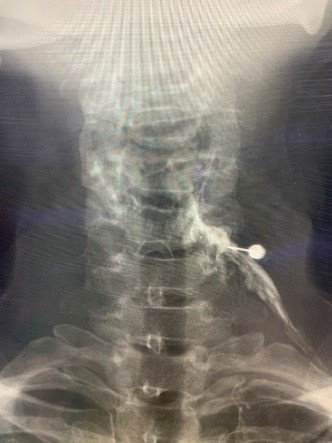

図 頚椎症による上肢の痛みに対する神経根ブロック

神経ブロック注射  (腰や首の神経根ブロック、坐骨神経ブロック、仙骨裂孔硬膜外ブロックなど)痛みの原因となっている神経や神経叢に直接麻酔薬やステロイド等を注入することで、痛みを軽減または遮断します。